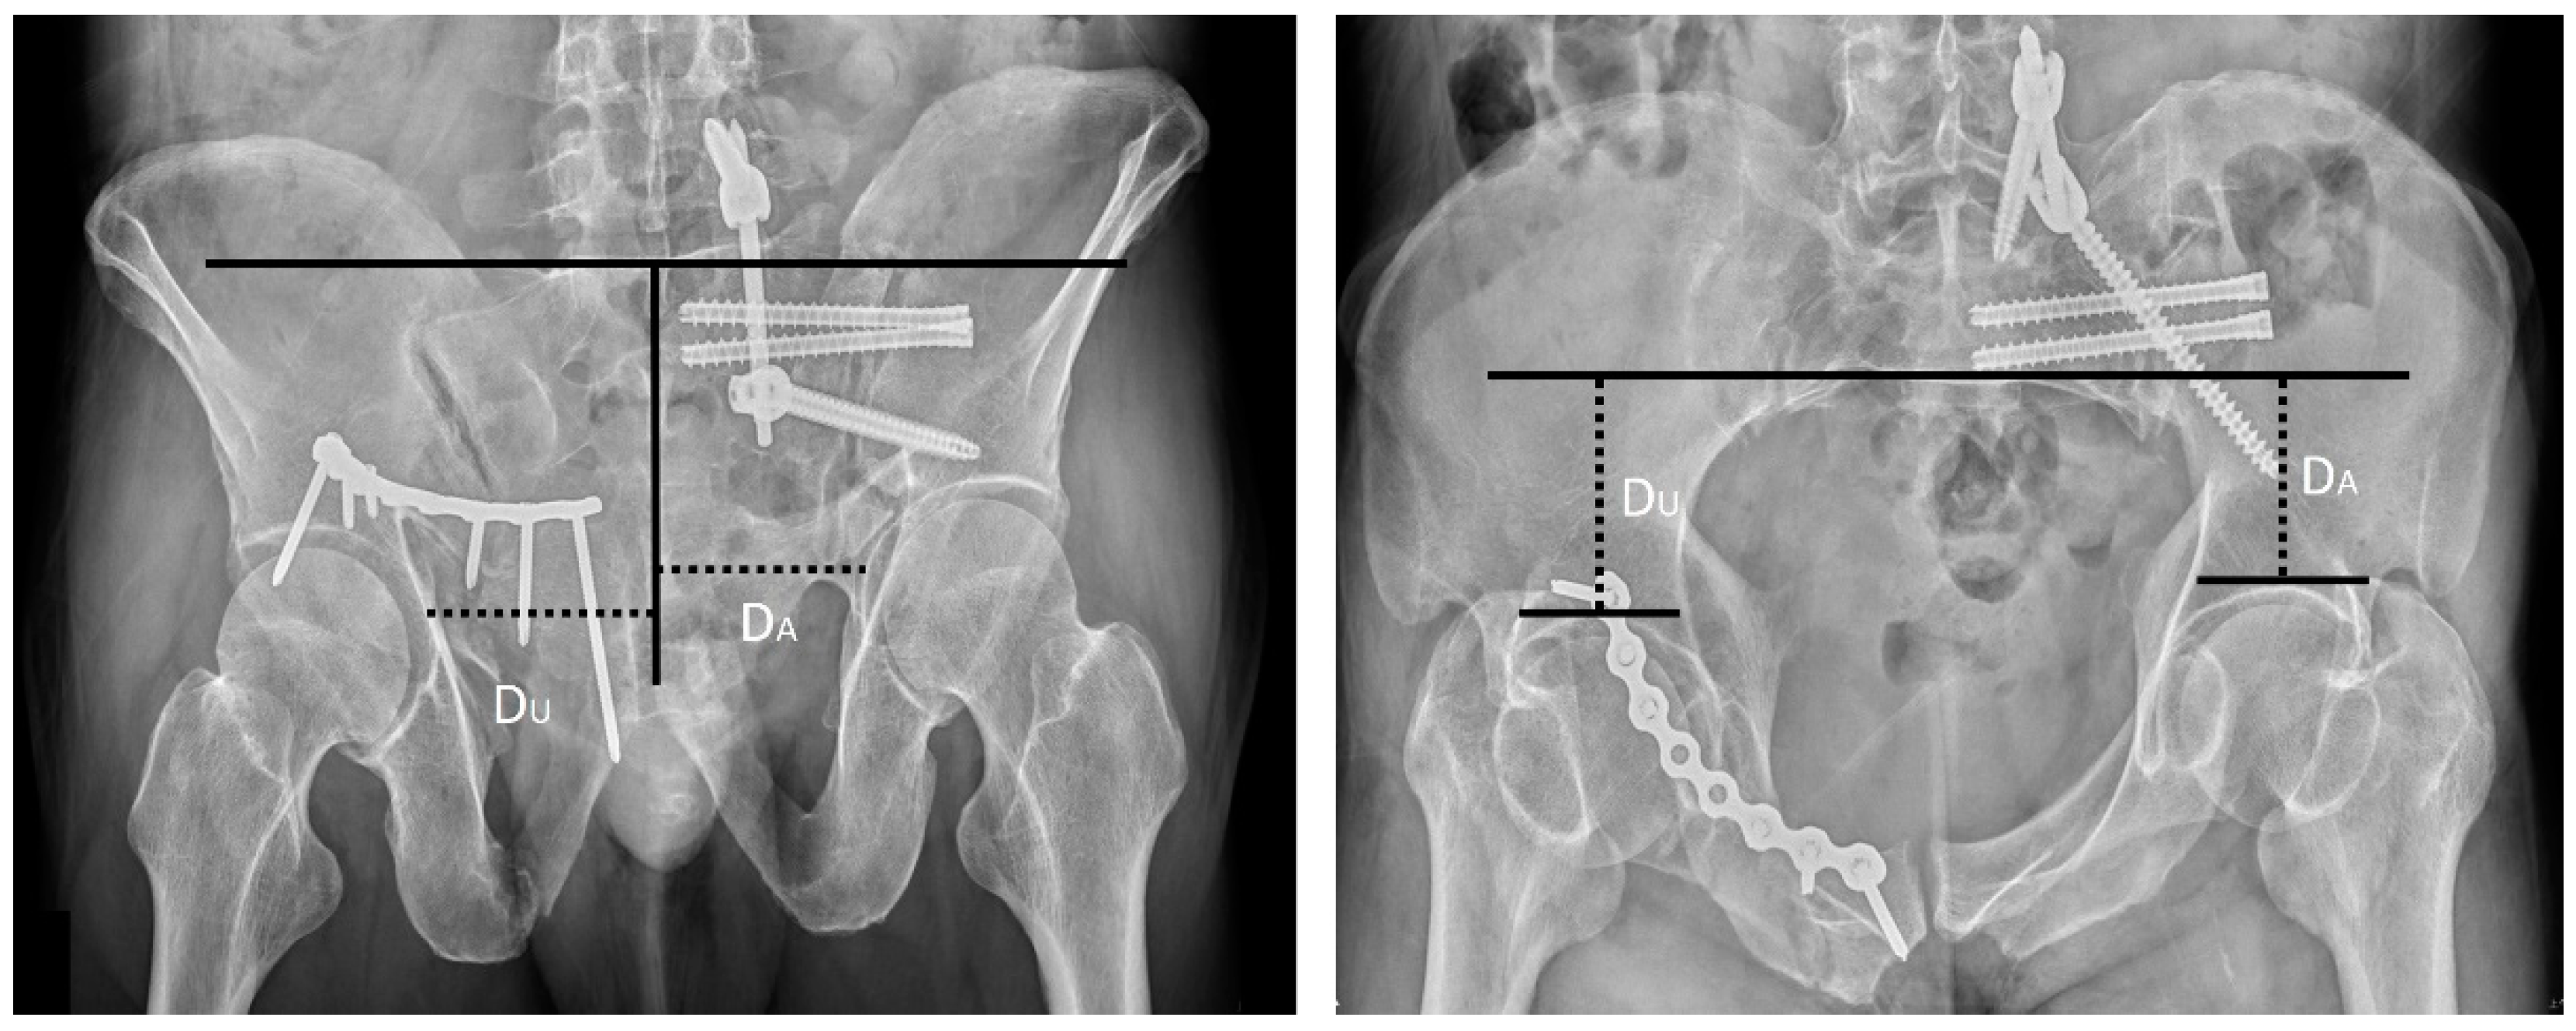

| Sagi et al., 2009 | Inlet and outlet ratio Method (Sagi Method) [11] | On the inlet view, we drew a line across the anterior border of the sacrum, perpendicular to the spinous processes. The perpendicular distance from this line to the subchondral bone of each acetabulum was measured, and a ratio was then calculated, with the affected side of pelvis set as the numerator. A similar ratio was obtained for the outlet view by drawing a line parallel to the superior end plate of S1, perpendicular to the spinous processes. The perpendicular distance from the reference line to the subchondral bone of each acetabulum was measured, and a ratio was then calculated, with the affected side of pelvis set as the numerator (Figure 3). |

| Lefaivre et al., 2009 | Absolute displacement method (ADM) [13] | This method was initially proposed by Lefaivre et al. in 2009. Observers were instructed to use preoperative pelvic AP, inlet, and outlet views. In each view, a horizontal line was drawn across the superior end plate of L5 as a reference line. If this was not visible in the film, the observers were asked to use the inferior end plate of L5 as a reference. Measurements were either parallel or perpendicular to this reference line. This line was used as the direction for horizontal measurements, or a line 90 degrees to this reference line was used for vertical measurements. Maximum displacements in the anterior and posterior pelvic rings were measured in each plane film. After completing the six measurements of the three preoperative films (anterior and posterior rings in each of the AP, outlet, and inlet views), the observers were instructed to measure the same anatomic locations in the postoperative plane films. Finally, the largest single measurements from the six preoperative and postoperative measurements were considered the preoperative and postoperative maximum displacements, respectively (Figure 5A,B). |